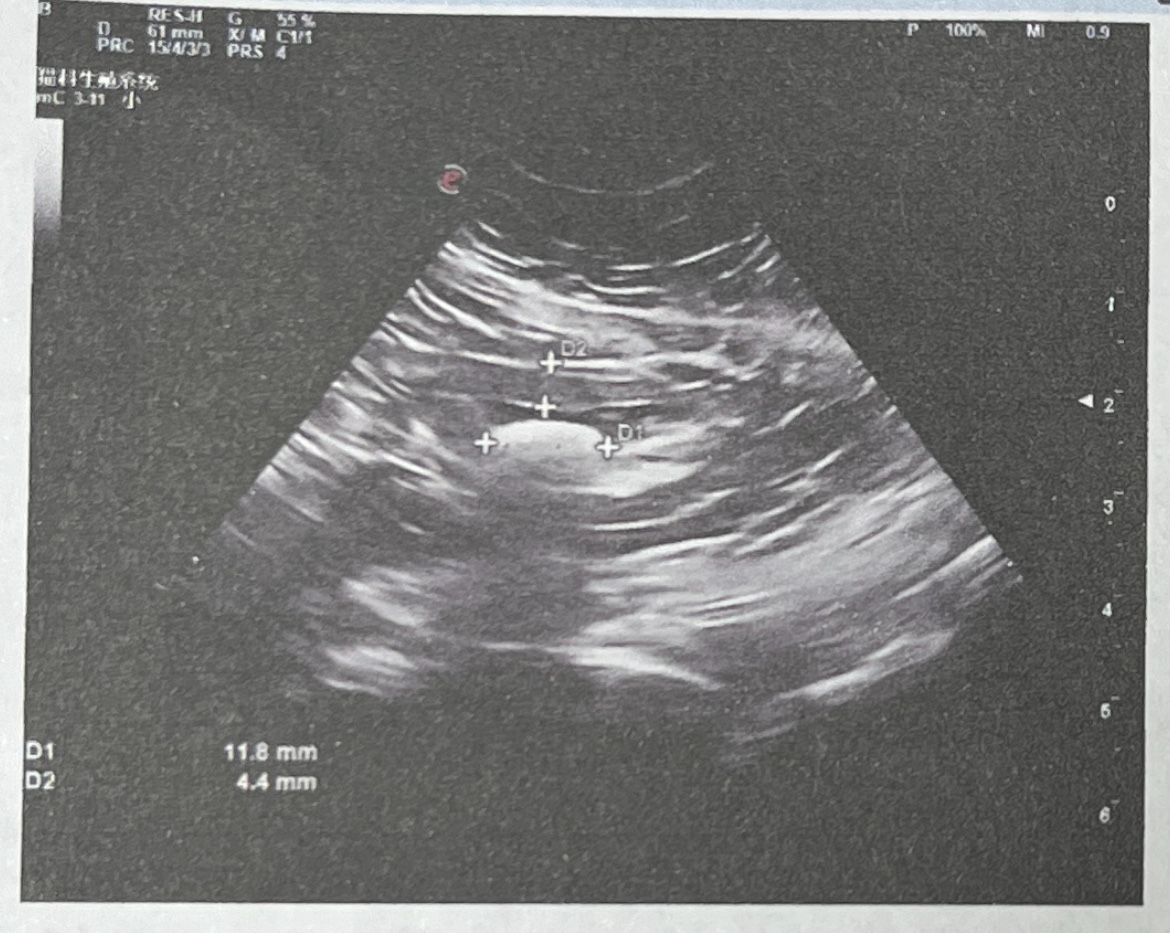

唉唉唉唉唉!一厘米的结石,明天手术!太可怜了!流浪时没少受罪,在家里两年了还是难逃一劫!上个月口炎刚恢复,这个月结石又犯了……宝宝